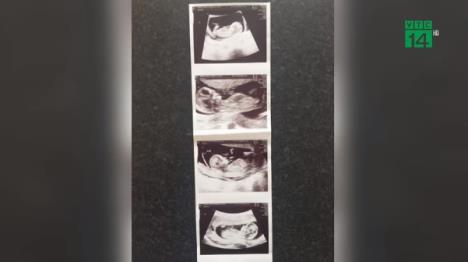

Naime, ona čeka tri devojčice, uključujući identične bliznakinje, dečaka sa svojim suprugom, Stivenom pošto se par odlučio na vantelesna oplodnju.

Ove godine odlučila je da ode na vantelesnu oplodnju i kod kuće je započela sa hormonskom terapijom pa je potom odletela na Kipar gde je u privatnoj poliklinici dala jajne ćelije na vantelesnu oplodnju Stivenovom spermom. Oplođena su četiri embriona koja su potom vraćena u njenu maternicu. Jedan embrio se prestao razvijati, a jedan se podelio.

Trejsi je trenutno u 25 nedelji, a kada uđe u 32 planira da se porodi carski rezom.